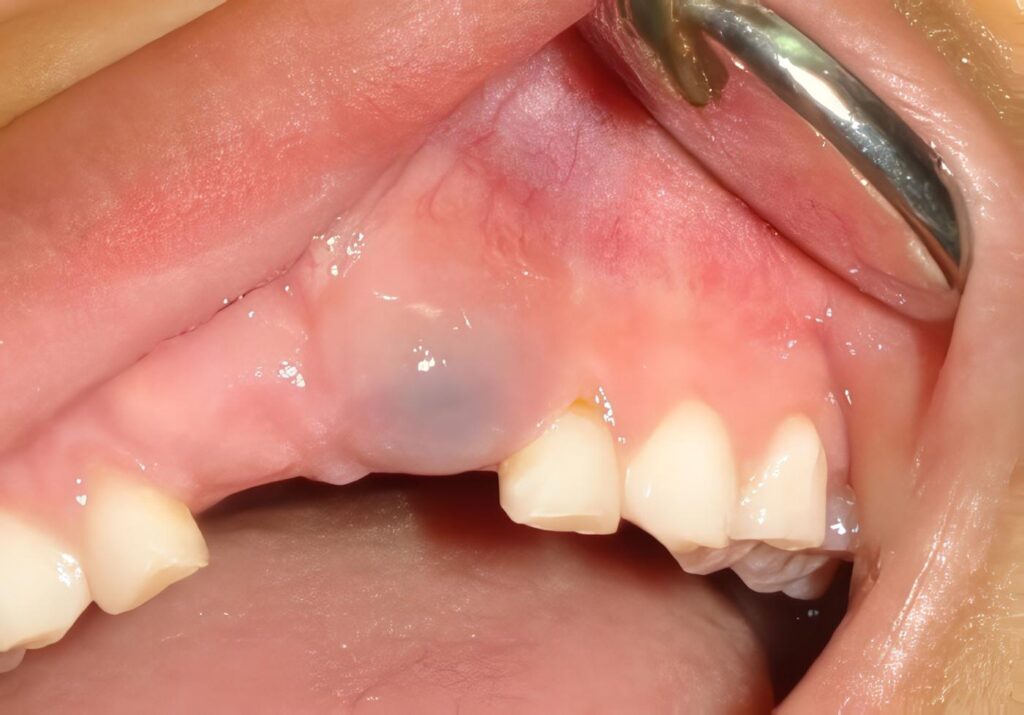

Las características clínicas de los quistes dentígeros son variadas; pueden presentarse como un abombamiento de la superficie vestibular o lingual, del mismo color de la mucosa y de consistencia firme o como una gran lesión que produce deformación facial, crepitante a la palpitación y de color violáceo.

Aumentan más rápidamente de tamaño en niños y adolescentes que en adultos, se pueden encontrar fístulas y drenaje de exudado purulento si están sobreinfectados. Pueden presentarse como lesiones únicas y se han descrito múltiples quistes dentígeros asociados con disostosis cleidocraneal y con un tipo de amelogénesis imperfecta no común, que cuna con numerosos dientes no erupcionados (2) (Fig. No. 1 y 2).

Fig. 2 Deformación intraoral y compromiso importante de estructuras dentarias relacionadas con la lesión quística.